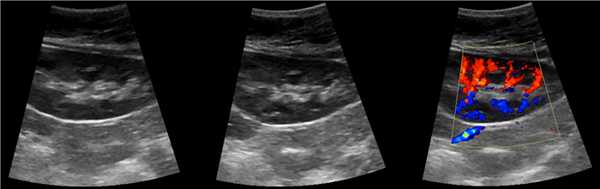

В положении пациента на спине по среднеключичной и переднеподмышечной линии выводим правую почку в соседстве с печенью, а левую почку вблизи селезенки. Оцените эхогенность почек. Корковый слой почки в норме изо- или гипоэхогенный по отношению к печени и гипоэхогенный по отношению к селезенке.

Рисунок. Эхогенность органов сравнивают на одном срезе. На УЗИ нормальная почка по соседству с печенью (1) и селезенкой (2). У детей до 6 месяцев паренхима почек в норме может быть гиперэхогенной по сравнению с печенью (3).

В нормальной почке пирамиды гипоэхогенные, корковое вещество и колонны Бертини изоэхогенны друг другу. В синусе располагается в норме невидимый ЧЛК, гиперэхогенная соединительная и жировая ткань, гипоэхогенные сосуды и вершины пирамид.

Когда различают пирамиды, корковое вещество, почечные колонны, то эхоструктура паренхимы почки не изменена. Если их не видно, то эхоструктура изменена за счет отсутствия четкой корково-мозговой дифференциации.

Рисунок. На УЗИ почка с неизмененной эхоструктурой: гипоэхогенный по отношению печени корковый слой и колонны Бертини, почти анэхогенные пирамиды, гиперэхогенный синус.

Мочеточник, малые и большие чашечки в норме не видно на УЗИ. Существует три типа расположения лоханок: интра-, экстраренальный и смешанный (частично внутри почки, частично вне ее). При интраренальном строение просвет лоханки в раннем возрасте до 3 мм, в 4-5 лет — до 5 мм, в пубертате и у взрослых — до 7 мм. При экстраренальном и смешанном типе строения — 6, 10 и 14 мм, соответственно. При переполненном мочевом пузыре лоханка может увеличиваться до 18 мм, но через 30 минут после мочеиспускания сокращается.

Рисунок. Независимо от наполнения мочевого пузыря на УЗИ видно лоханку смешанного (1, 2) и экстраренального (3) расположения.

Рисунок. У детей до 1 года на УЗИ синус почки определяется слабо, анэхогенные пирамиды можно ошибочно принять за расширенный ЧЛК (1). На УЗИ в воротах почки линейная гипоэхогенная структура похожа на расширенную лоханку (2); при ЦДК видно, что это сосуды (3).